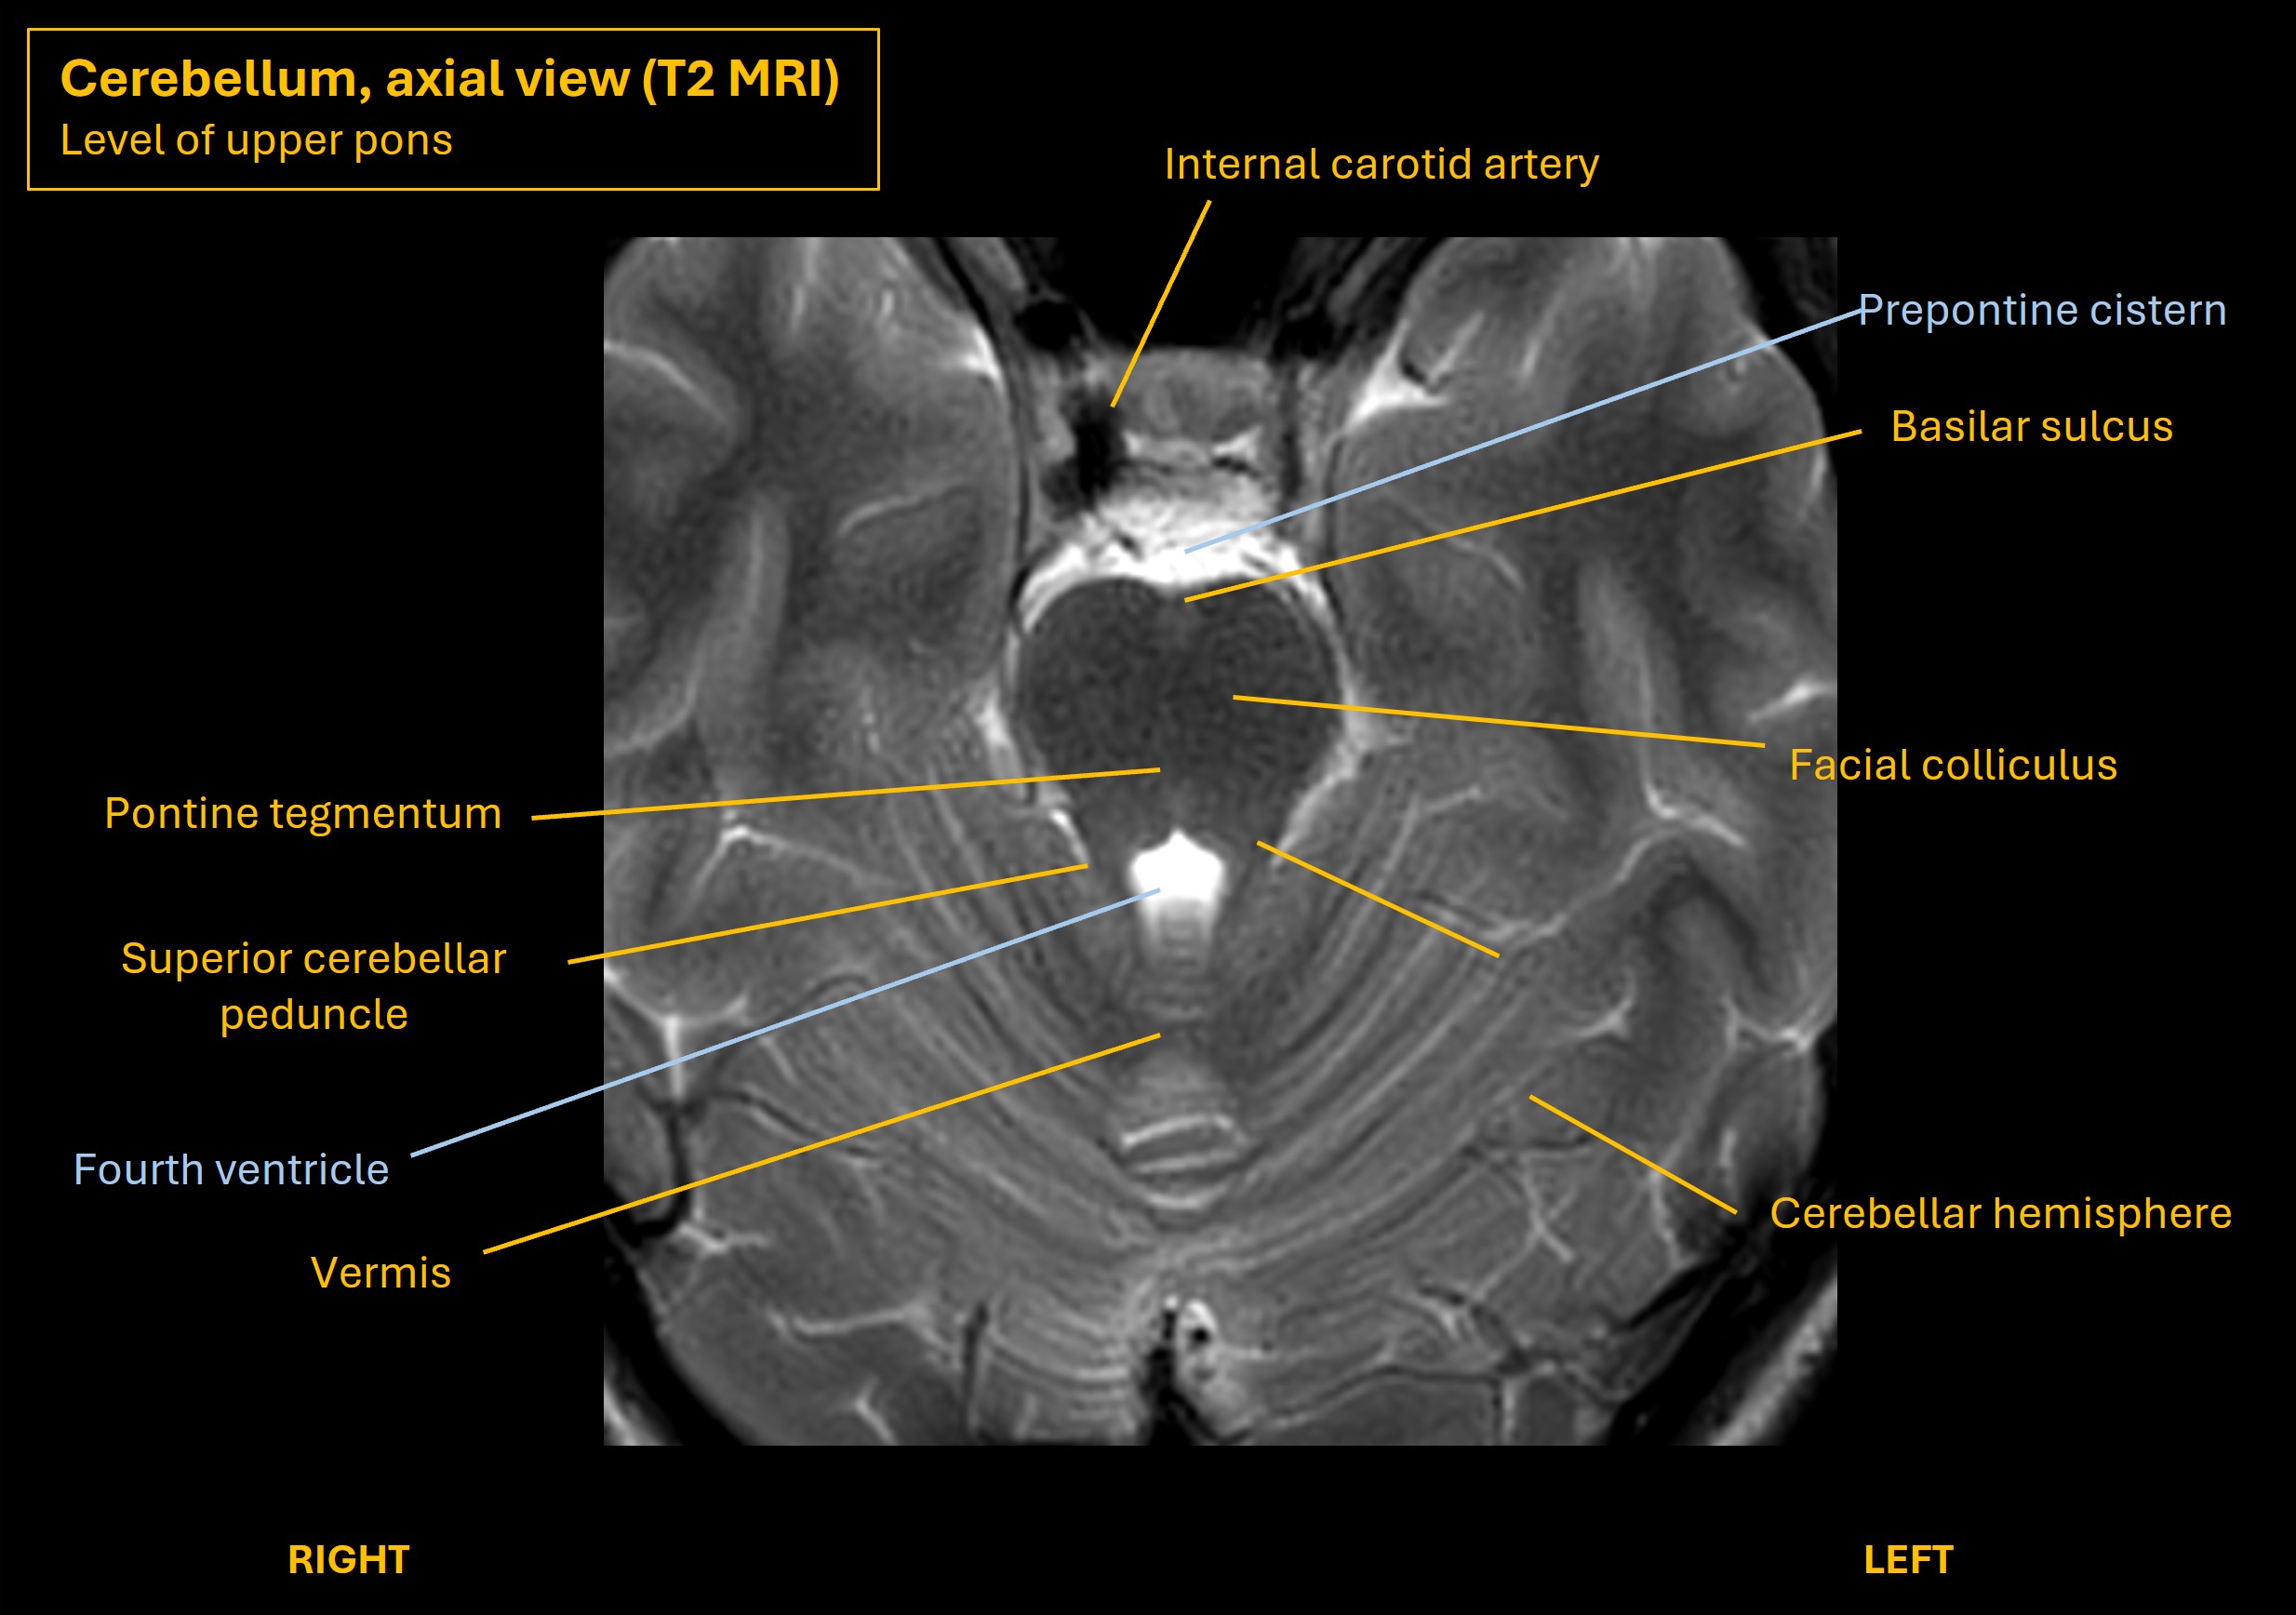

The images below show axial and sagittal views of the cerebellum and illustrate key features and relationships with the brainstem.

The cerebellum connects with the brainstem via the three peduncles - inferior, middle and superior. The middle is very large - forming two broad 'arms' either side of the pons. Many tracts enter and leave the cerebellum through these, involved in control of many functions - posture, balance, gait, targetted limb movements, eye movements and speech.

The left cerebral cortex parts involved in motor planning send corticopontine fibres to the left pons. These then project pontocerebellar fibres to the cerebellum via the middle cerebellar peduncle (MCP), otherwise known as the brachium conjunctivum. There is decussation – the left fibres pass via the right MCP to the right cerebellar hemisphere.

The efferent pathway then begins – the cerebellar hemisphere projects to the dentate nucleus, then fibres pass out via the superior cerebellar peduncle (SCP) and decussate again. They then go to the ventrolateral (VL) nucleus of the thalamus, or pass via the red nucleus as an intermediate stop before going to the thalamus; these fibres are called dentatorubrothalamic fibres. Finally, the VL projects thalamocortical fibres which go to the motor cortex. From here the motor cortex projects to the contralateral body via the corticospinal tract.